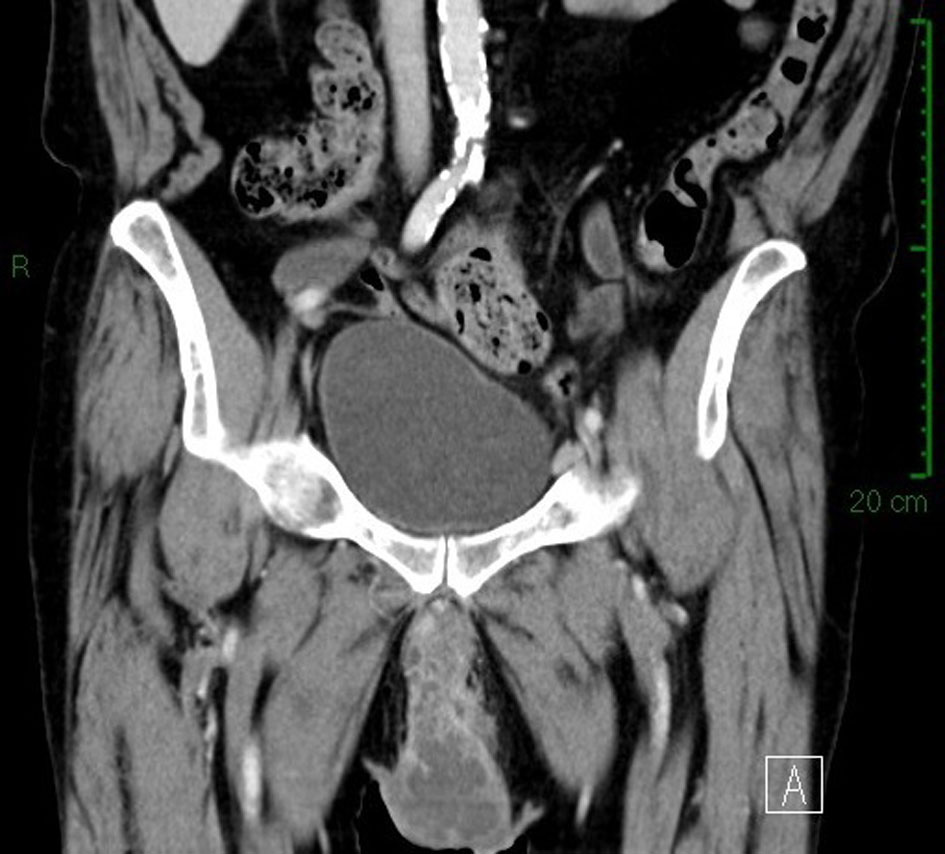

We admitted an 81-year-old man to our hospital for fever and a scrotal ulcerative lesion with clear signs of infection. His past medical history included bilateral cryptorchidism surgically treated in young age, inguinal hernia and hypertension. Scrotal examination showed an indolent malodorous scrotal ulcer, discharging abundant purulent and mucinous fluid. We performed a bacterial swab and cold biopsy and started empirical antibiotic therapy. After a few days, fever disappeared and white blood cells dropped within normal range. Bacterial swab was positive for Citrobacter farmeri and Staphylococcus saprophyticus, therefore, we started a targeted antibiotic therapy. Biopsy showed atypical cells, macrophages, bacteria and mucin. Abdomen/pelvis CT scan (Fig. 1) revealed a massive left inguinal hernia containing fat and bowel and a small contralateral inguinal hernia containing only adipose tissue. CT showed a large perineal and scrotal area with multicystic aspects and air microbubbles, as a result of an abscess (Fig. 2, 3); no intraperitoneal or retroperitoneal fluid was observed.

![]() Click for large image | Figure 1. CT scan image: sagittal section of scrotal area showing multicystic aspect of neoplasm. |